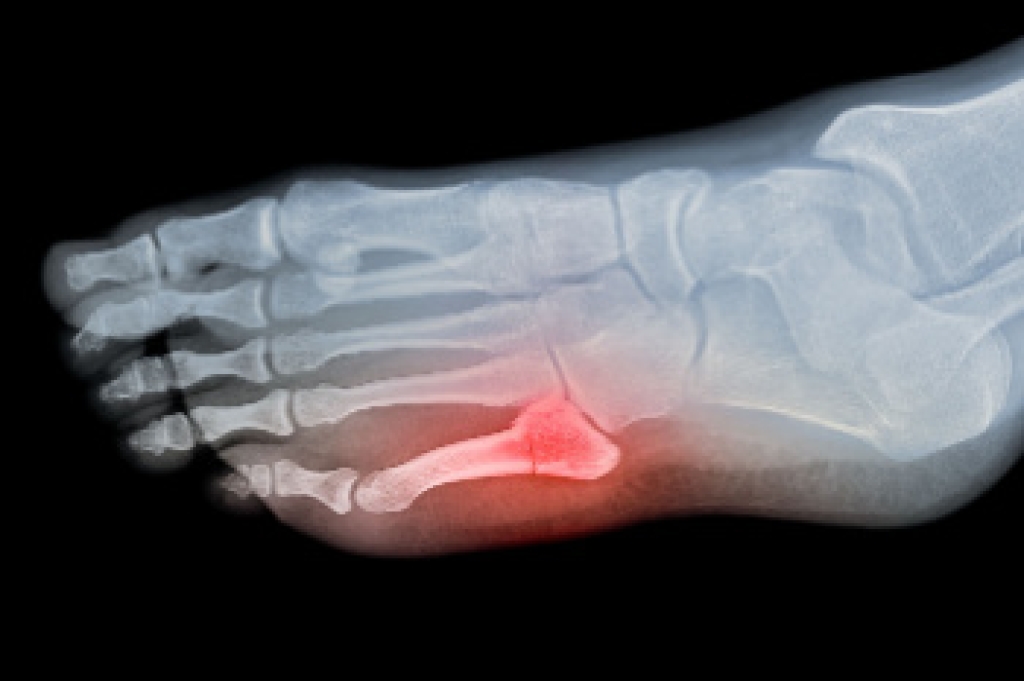

Diagnosing foot fractures, particularly metatarsal shaft fractures, involves a thorough evaluation by a podiatrist. These fractures commonly result from direct trauma, overuse, or sudden twisting movements. Symptoms patients typically experience include localized pain, swelling, bruising, and difficulty bearing weight on the affected foot. A physical examination is essential for assessing tenderness and deformity. Diagnostic imaging, primarily an X-ray, is used to confirm the fracture and determine its severity. In some cases, a CT scan or MRI may be recommended for a more detailed view of the injury. Timely and accurate diagnosis is essential for appropriate treatment, which may include rest, immobilization, or in severe cases, surgery. If you have broken your foot, it is suggested that you consult a podiatrist who can determine the type of fracture and offer appropriate treatment solutions.

A broken foot is caused by one of the bones in the foot typically breaking when bended, crushed, or stretched beyond its natural capabilities. Usually the location of the fracture indicates how the break occurred, whether it was through an object, fall, or any other type of injury.

Treatment for broken bones varies depending on the cause, severity and location. Some will require the use of splints, casts or crutches while others could even involve surgery to repair the broken bones. Personal care includes the use of ice and keeping the foot stabilized and elevated.